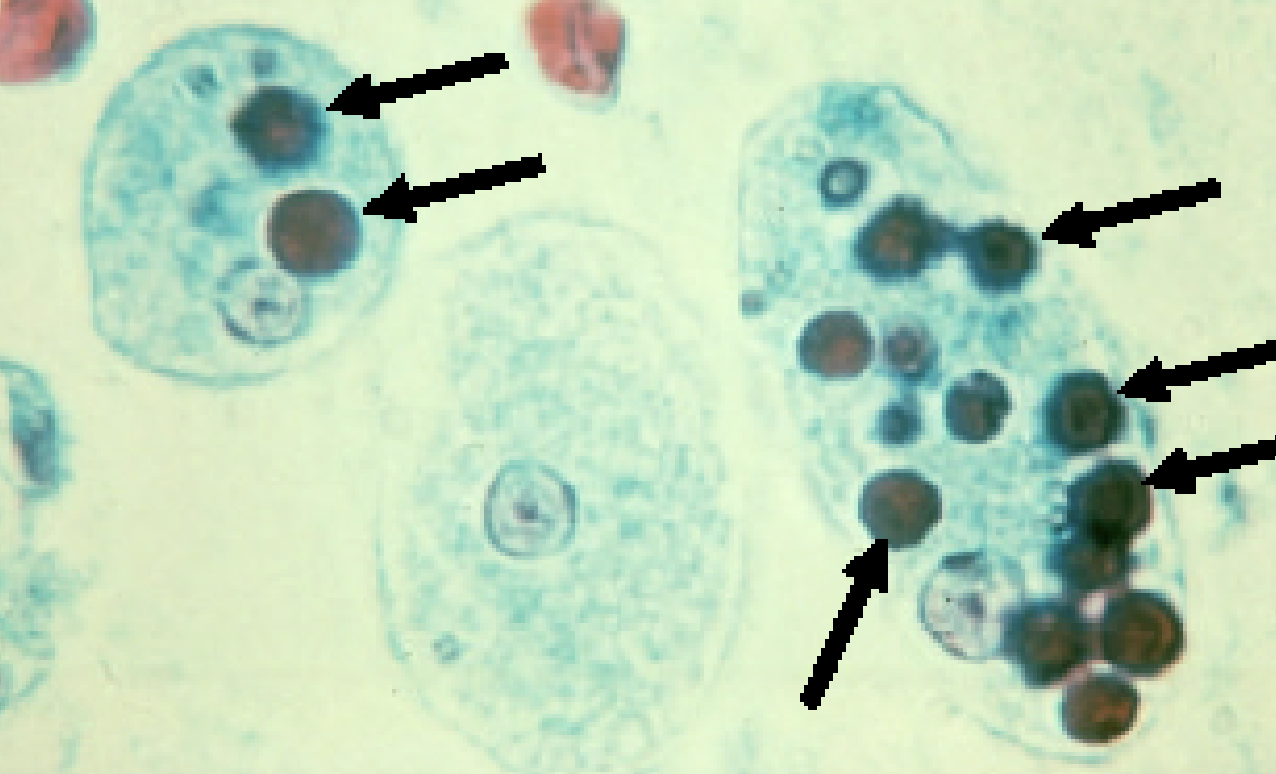

Entamoeba coli

E. coli troph form

E.coli troph form

What parasite has splintered chromatoidal bars and may contain glycogen vacuoles and has up to 8 nuclei?

E. coli

E. coli cyst

E.coli cyst